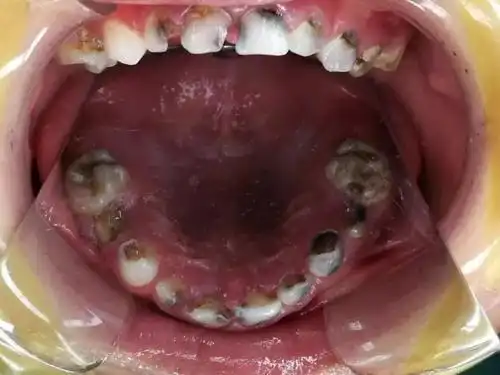

四周岁小孩蛀牙,时不时喊牙疼,一个月前幼儿园体检也查牙了,好几个

女儿七岁,蛀牙这样严重,有什么办法缓解吗

小孩蛀牙怎么办5岁儿童烂牙到底要不要补

儿童蛀牙疼痛怎么缓解

严重龋齿的图片_有来医生

儿童龋齿形成的图片_有来医生

2岁宝宝牙齿全烂光,6岁男孩牙疼得"死去活来"!别等孩子蛀牙了才后悔!

糖吃多了会长蛀牙,但这个3岁宝宝满口"黑牙",竟是因为